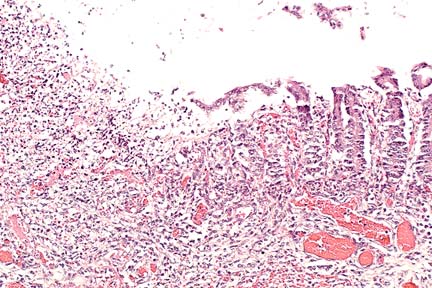

Acute ulcerative colitis in a foal treated with castor oil (HE, 200X, 50K).

Contributor's Diagnosis and Comments: Colitis, severe, focally extensive, acute, erosive and necrotizing. Castor oil-induced superficial colitis, with secondary probable endotoxin-induced submucosal thrombosis, inflammation, and mucosal necrosis.

A large area of the submucosa is thickened by edema, hemorrhage, acute inflammatory cell infiltration, lymphatic distention and venous and capillary thrombosis. The overlying mucosa in necrotic, and there are multiple surface clumps of bacteria. Adjacent viable areas of mucosa have flattened superficial epithelium, inflammatory cells between membrane and epithelium and capillary thrombosis. Severe hemorrhagic foci are present in the muscularis and serosa.

Acute superficial enterocolitis is reported in the literature following the experimental administration of castor oil to ponies. In the cecum and ventral colon, there is extensive erosion of superficial epithelium between crypts, with fibrin, neutrophils and cell debris on the denuded basement membrane. By 48 hours post ingestion, there is partial restitution of surface epithelium by flattened epithelial cells extending from the necks of crypts. Fragmented necrotic debris is sometimes present within macrophages within the lamina propria. Mucosal venules beneath the erosions are plugged with fibrin, and there is general mucosal venous congestion and distention of submucosal lymphatics.

AFIP Diagnosis: Colon: Colitis, necro-ulcerative, acute, focally extensive, severe, with hemorrhage, fibrin thrombi and fibrinoid vascular necrosis, Arabian, equine.